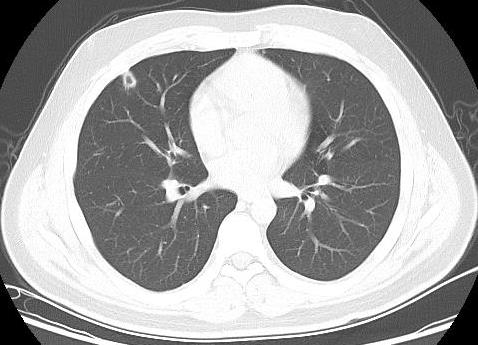

患者男性,21岁,主因“间断发热、寒战伴头晕头痛2周”于2021年11月18日急诊收入院。患者诉2周前进食烧烤后出现发热,体温最高可达42℃, 伴畏寒、寒战、咽痛、头晕、头痛、乏力,就诊于本院耳鼻喉科后,查体见扁桃体有脓点,快测降钙素原(procalcitonin,PCT)为37.27 ng/mL,胸部CT检查未见异常,考虑诊断为“急性化脓性扁桃体炎”,先后给予左氧氟沙星、阿奇霉素抗感染及甲泼尼龙控制炎症后上述症状未见明显好转,为进一步治疗,收入急诊病房治疗,既往体健,入院时查体:体温41℃,脉搏98次/min,呼吸频率23次/min,血压120/60 mmHg(1 mmHg=0.133 kPa),患者神志清楚,急性病容,精神较差,颈部浅表淋巴结触及肿大,右侧较大约2.0 cm ×0.5 cm,左侧较大约1.3 cm×0.7 cm,质软,活动度好,界限清楚,有压痛,表面皮肤无红肿,无破溃,双肺呼吸音清,未闻及干湿性啰音,心脏听诊无杂音,腹软,无压痛及反跳痛,双下肢无水肿。血常规检查白细胞计数10.49×109/L, 中性粒细胞百分比94.6%,血红蛋白120 g/L, 血小板计数107×109/L,PCT 42.83 ng/mL,白介素6(interleukin, IL-6)980.30 pg/mL,C反应蛋白211 mg/L,G试验、GM试验阴性。胸部CT检查示右肺上叶可见一单发实变影,其内可见空洞(图 1)。根据病史、查体和辅助检查考虑诊断为肺脓肿,给予注射用哌拉西林钠他唑巴坦4.5 g Q8h治疗,入院第2天,患者仍有发热,体温最高38.7℃,给予对症处理,入院第3天患者体温峰值有所下降,体温维持在37~38℃,考虑抗炎有效,痰培养结果回报为纹带棒杆菌,草绿色链球菌(奈瑟菌属),考虑这2种细菌为皮肤或口腔的正常菌群,为条件致病菌,该细菌导致发热的可能性较小,继续给予哌拉西林钠他唑巴坦治疗。入院第5天血培养回报血液中找到坏死梭杆菌,考虑为血流感染。加用甲硝唑1 g每8 h一次抗感染治疗,复查血常规白细胞计数8.14×109/L, 中性粒细胞百分比81.5%,血红蛋白120 g/L, 血小板计数246×109/L,PCT 3.43 ng/mL,IL-6 13.04 pg/mL,C反应蛋白5 mg/L,炎性指标较前明显下降,考虑抗炎治疗有效,继续目前抗生素治疗。入院第10天患者体温仍有低热,体温36.5~37.5 ℃,复查胸部CT见双肺多发小结节,双肺多发空洞病变,考虑炎性可能(图 2)。颈静脉超声检查提示患者左侧颈内静脉血栓形成,给予依诺肝素0.4 mL每12 h一次抗凝治疗,根据血培养结果、胸部CT表现和颈静脉超声结果,考虑该患者诊断为坏死梭杆菌导致Lemierre综合征(Lemierre syndrome, LS)。用哌拉西林钠他唑巴坦联合甲硝唑治疗后仍有低热,化验检查PCT为0.30 ng/mL,IL-6为3.52 pg/mL,C反应蛋白为3 mg/L,胸部CT示肺部空洞较前增加,考虑感染未完全控制,改为调整抗生素为比阿培南0.6 g每12 h一次联合甲硝唑1g每8 h一次抗感染治疗,治疗1周后患者体温恢复正常,CT检查示双肺多发空洞消失,残留少量索条影(图 3),患者病情好转出院,出院带药给予口服甲硝唑联合阿莫西林抗感染治疗,利伐沙班抗凝治疗,随诊2周后复查胸部CT正常。

| 双肺空洞病变 图 2 入院第10天胸部CT |

LS的致病菌主要为坏死梭杆菌,因此LS也被称为坏死梭杆菌病,其他致病菌包括核杆菌、类杆菌、链球菌和葡萄球菌等[5]。坏死梭杆菌为厌氧革兰阴性多形态杆菌,广泛存在于人类和动物的口腔、上呼吸道、胃肠道和泌尿生殖道的正常菌群。坏死梭杆菌可以产生白细胞毒素、内毒素、溶血素和血细胞凝集素等,白细胞毒素和溶血素与脓肿形成相关,血细胞血凝素可引起动静脉血栓形成,可导致转移性脓肿,弥漫性血管内凝血和血小板减少也与此有关[6]。患者起初为咽部感染,然后通过咽旁间隙侵袭至颈内静脉,形成颈内静脉血栓,脓毒性栓子随着血流播散至肺部,引起肺部脓肿和肺栓塞。本例患者刚发热时胸部CT正常,门诊给予喹诺酮类药物和大环内酯类药物治疗2周后,入院时胸部CT示患者右肺中叶单发实变影,其内可见空洞样变,后随病情发展,胸部CT示双肺多发肺空洞样变,符合LS的临床表现。LS最初表现为喉咙痛或颈部疼痛, 但可出现多种非特异性症状, 如全身僵硬、寒战、发热、颈部淋巴结肿大、眼眶疼痛、骨/关节疼痛、四肢无力、恶心、呕吐等胃肠道症状。最初感染1周后,可以在血液中找到细菌,然后在颈静脉内脓毒性血栓形成,可以肺内形成肺脓肿和脓胸,也可以累及关节[7]。